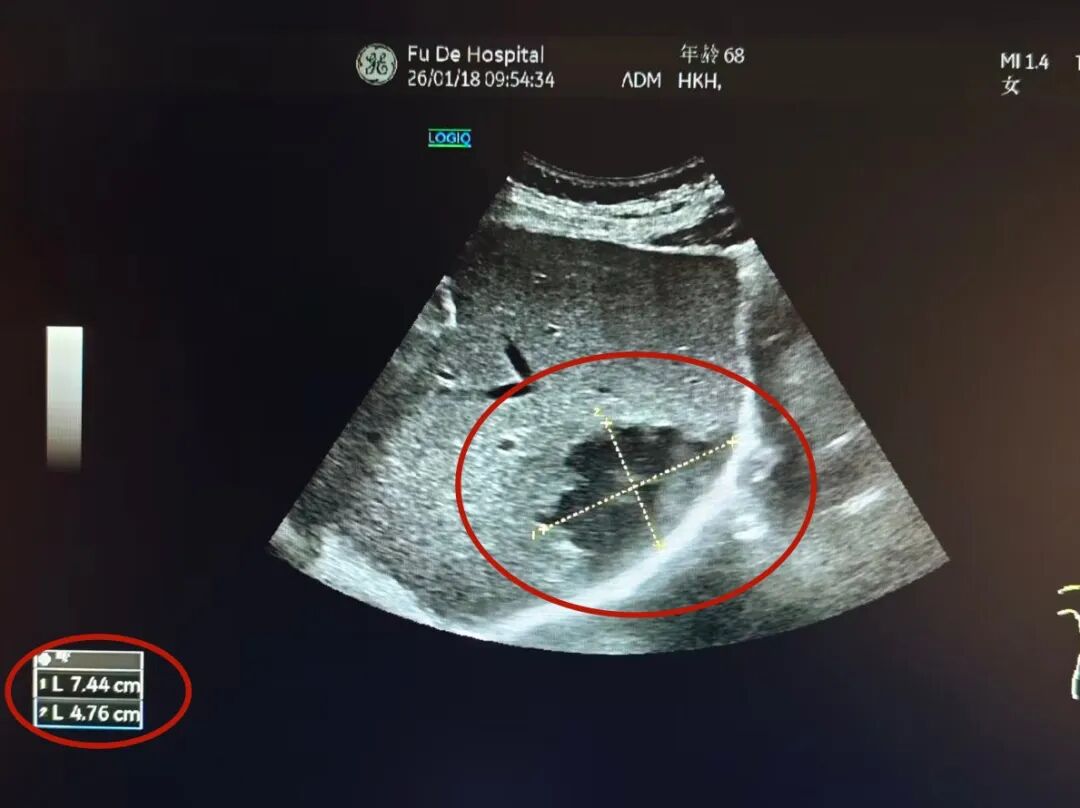

接诊后,通过详细询问病史,结合症状及糖尿病基础,综合内科主任陈星主治医师为其进一步安排肝胆胰脾彩超,结果显示,黄阿姨肝脏内有 一大小近7公分的脓肿, 这正是导致她持续腹痛的“元凶”。

术后,综合内科团队给予对症治疗,不久黄阿姨的症状便明显改善,精神状态也日渐好转。 复查彩超显示,肝脓肿已明显缩小。 “现在感觉舒服多了,整个人都轻松了,真的太感谢陈主任、石主任和医护团队了!”黄阿姨感激之情溢于言表。